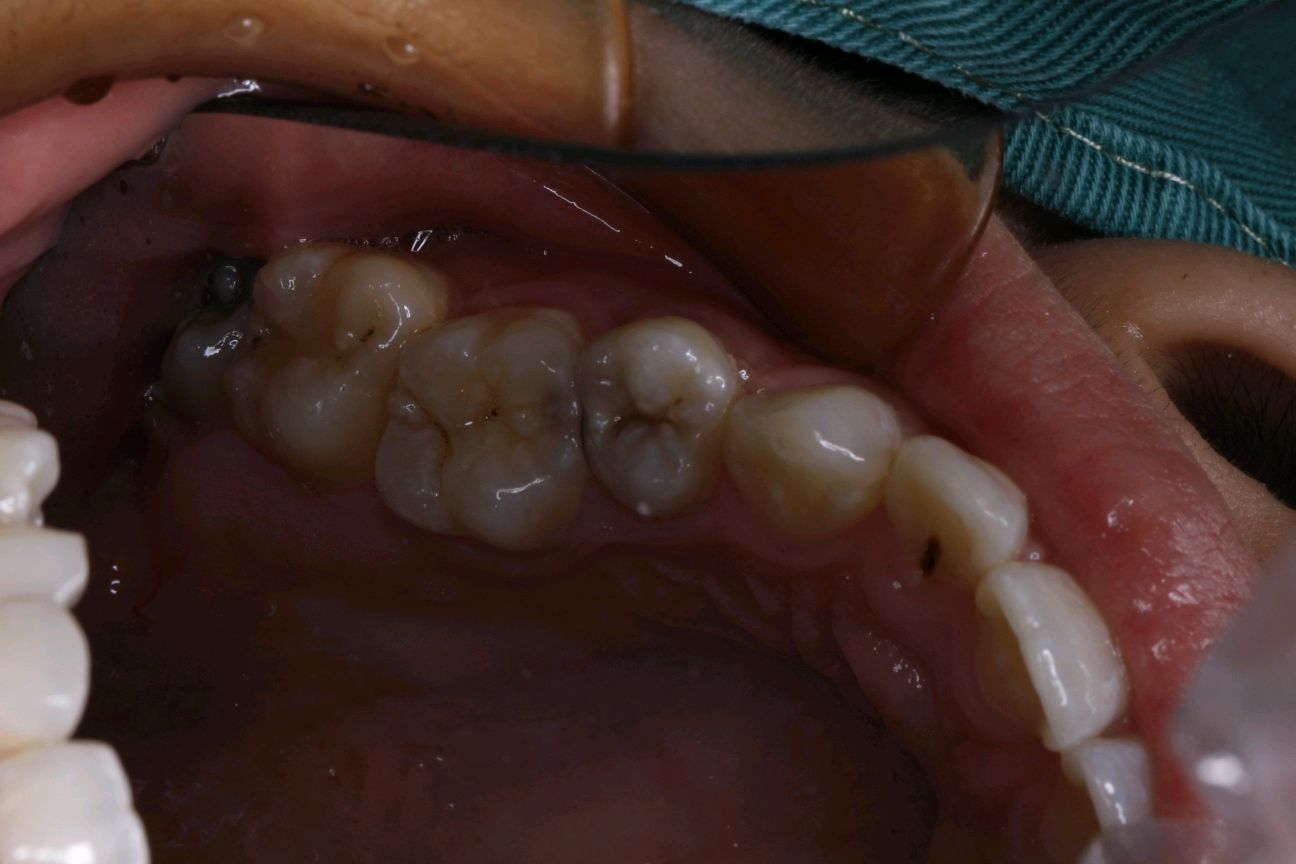

术后